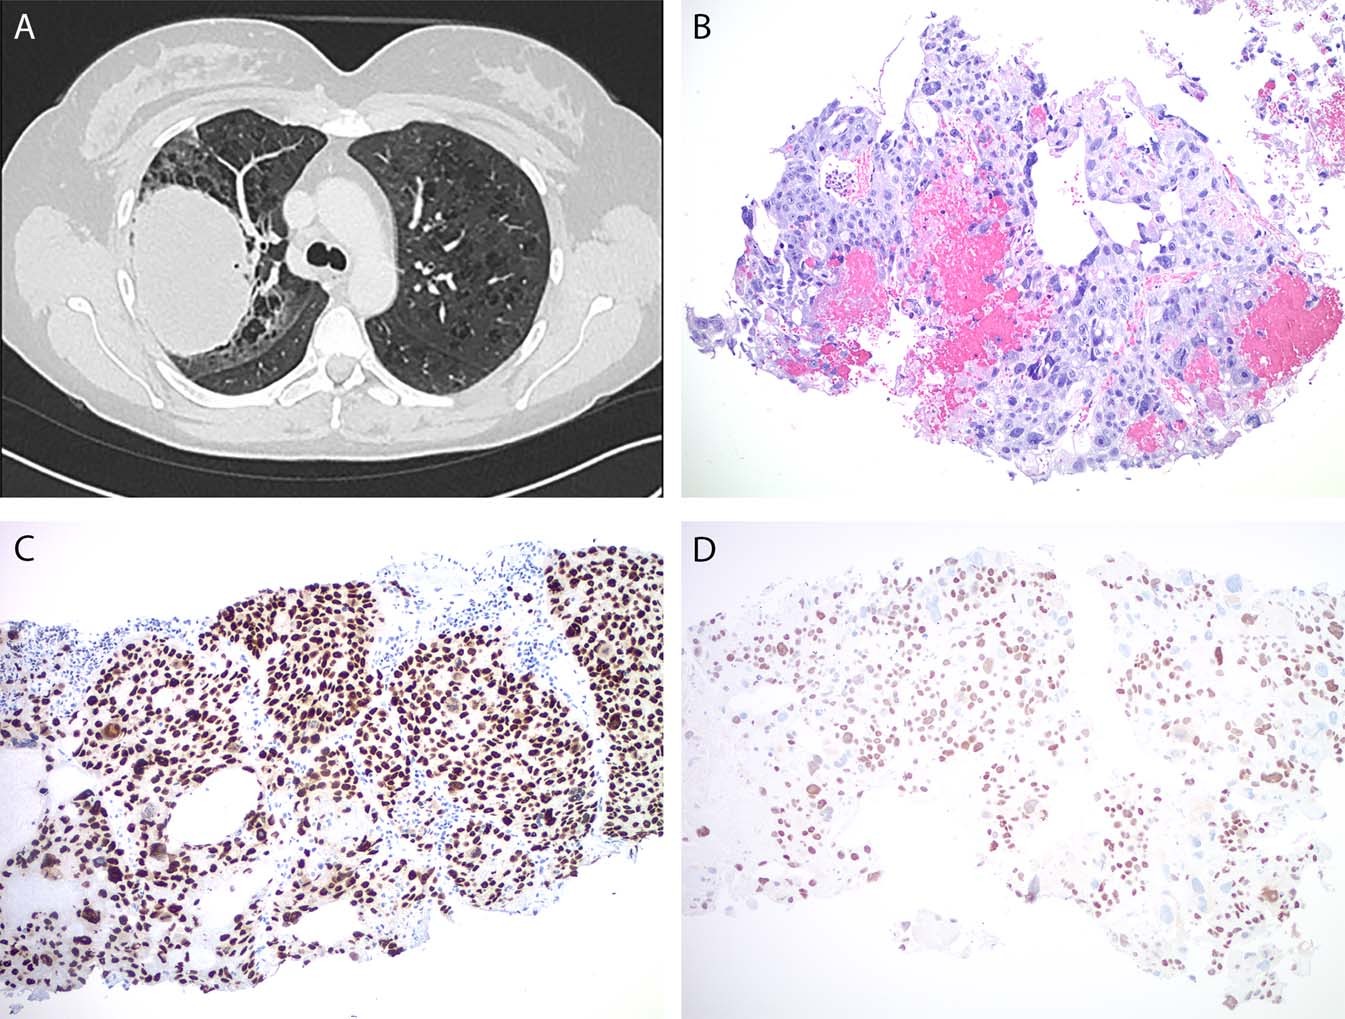

Fig. 3

From: Precision genotyping diagnosis of lung tumors with trophoblastic morphology in young women

Case #2. CT of the chest identified a large solitary lung mass in the right upper lobe with right hilar lymphadenopathy and emphysema (a). Core needle biopsy of the lung mass showed solid sheets of tumor cells with marked nuclear pleomorphism, multi-nucleation, and focal hemorrhage and necrosis (b). GATA3 immunostain was strongly and diffusely positive (c) and p40 immunoreactivity was present in the majority of tumor cells (d)